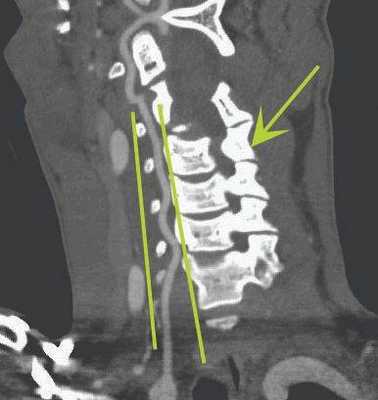

КТ-ангиограмма кровеносных сосудов в области шеи. Позвоночная артерия находится между вертикальными линиями. Стрелка указывает на позвоночник